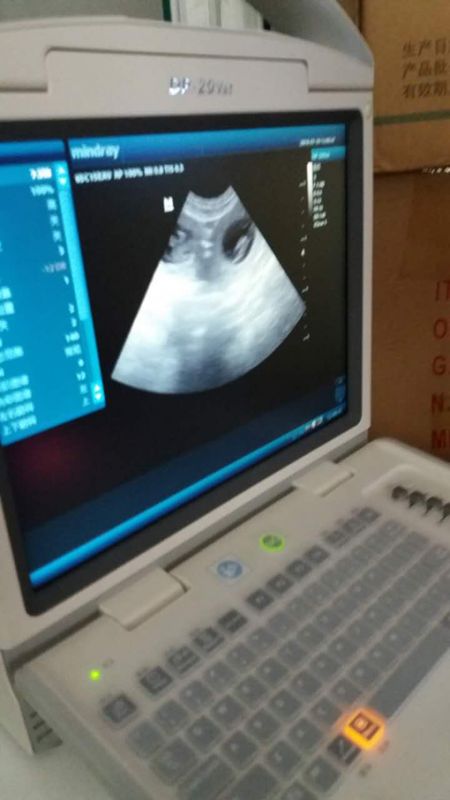

妮克 怀孕30天B超可以看到小胎儿了